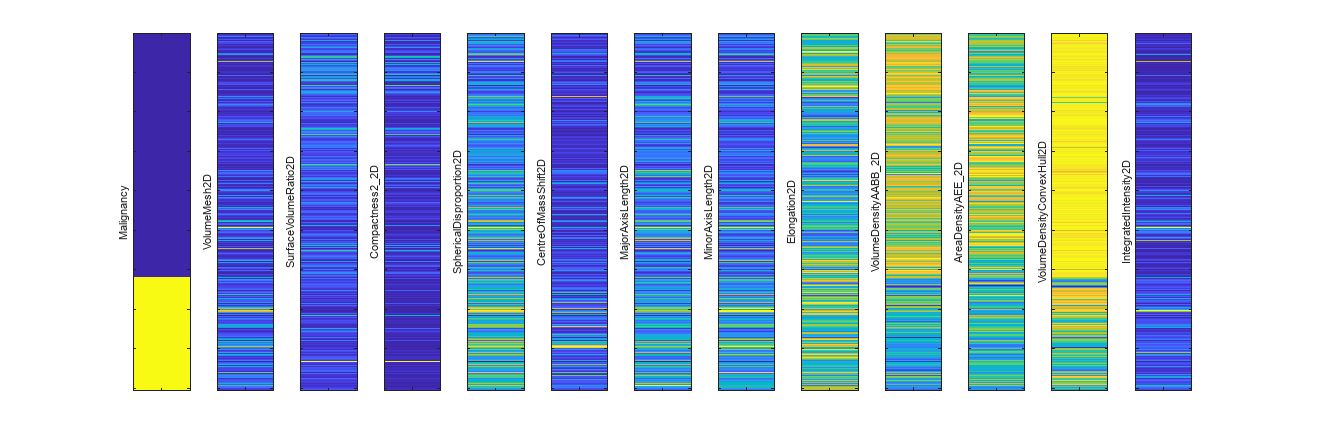

Visualize Radiomics Features

Compute the number of features after feature selection.

f = size(radiomicsFeaturesTrain,2)

f = 12

Create a logical vector that corresponds to the labels of the training data, representing benign labels with the value false and malignant labels with the value true.

labelsTrainLogical = labelsTrain == "malignant";Visualize each selected feature for the training data alongside their labels. The first bar in the visualization shows the ground truth classification of the training data, with benign tumors indicated in blue and malignant tumors indicated in yellow. The rest of the bars show each of the selected features. Note that, although the colormap of each feature is different, the trend of each feature changes where the malignancy changes. For example, for the VolumeDensityConvexHull2D feature, the bottom portion of the bar corresponding to malignant tumors is more blue than the upper portion corresponding to benign tumors.